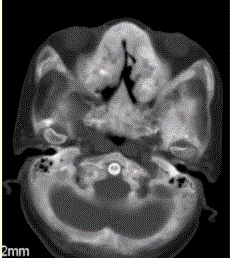

问题 患者女,25岁,左侧面部肿块,突眼10余年。CT表现如下图。 关于骨纤维异常增生症,正确的表述是

选项 A.以骨纤维变性为主要病理学表现 B.只累及单骨,是一种自限性疾病 C.多为女性 D.患者可表现为“骨性狮面” E.影像学检查可见“竖发征” F.病变可表现为丝瓜酪改变

答案 ACDF